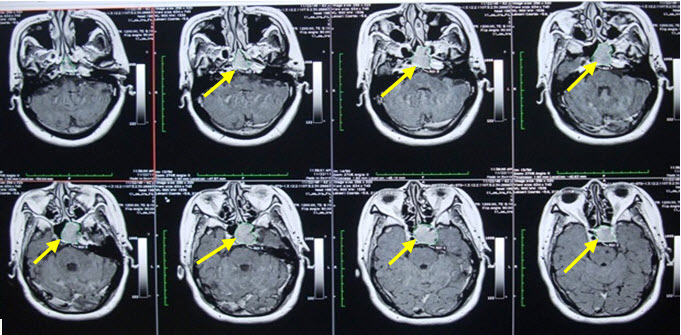

Sau xạ phẫu: Bệnh nhân u tuyến yên được theo dõi sát, khám định kỳ 1 tháng, 3 tháng, 6 tháng, 12 tháng, 24 tháng, 36 tháng…, đánh giá các triệu chứng lâm sàng, cận lâm sàng, đối chiếu trước và sau điều trị…

3. Theo dõi đánh giá sau xạ phẫu u tuyến yên

Dựa vào:         Triệu chứng cơ năng.

Triệu chứng thực thể.

Xét nghiệm hormone tuyến yên.

Kích thước khối u.